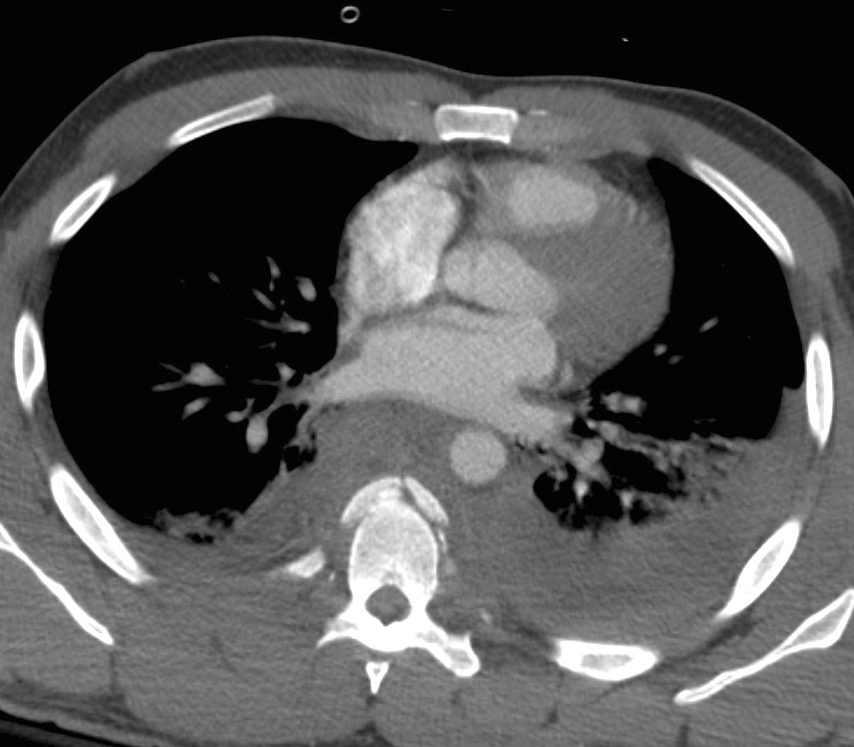

Gallery Blunt Chest Trauma Spine trauma Case 7c

Case 7c